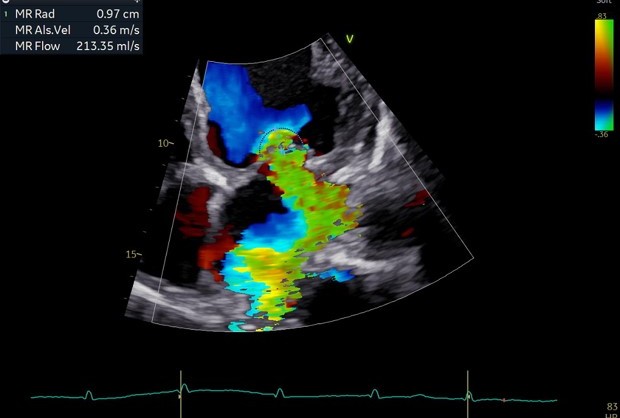

反流情况

术前TEE及左房压

1区

1区带彩

2区

2区带彩

3区

3区带彩

3D

3D带彩